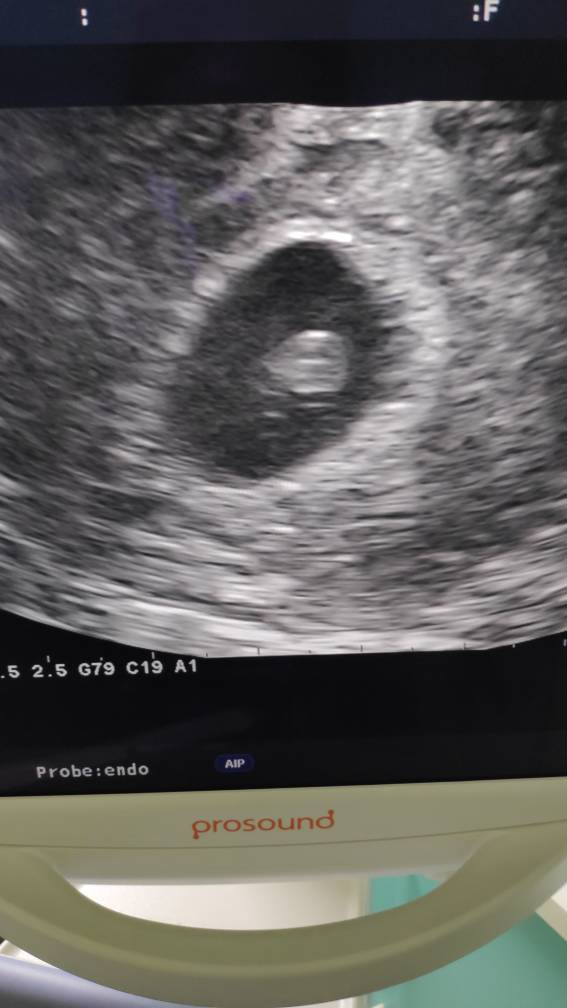

A to fotka

IMG_20200513_131254.jpeg

Jestem taaaaakaaaa szczęśliwa [emoji7][emoji3059][emoji3590]

Jest serducho [emoji3590] waliło jak oszalałe - mały człowiek we mnie mieszka [emoji7]

Słabo go trochę widać na zdjęciu przez moją tkankę tłuszczową hehe... trudno, najwyżej nie bedzie miec ladnych zdjęć w brzuchu póki co [emoji13]

Termin z USG na 31.12 - 01.01. [emoji3059] Będzie impreza [emoji4]

Za nic nie pamiętam ile ma długości...8,4 mm? Już nie słuchałam taka byłam zakręcona.